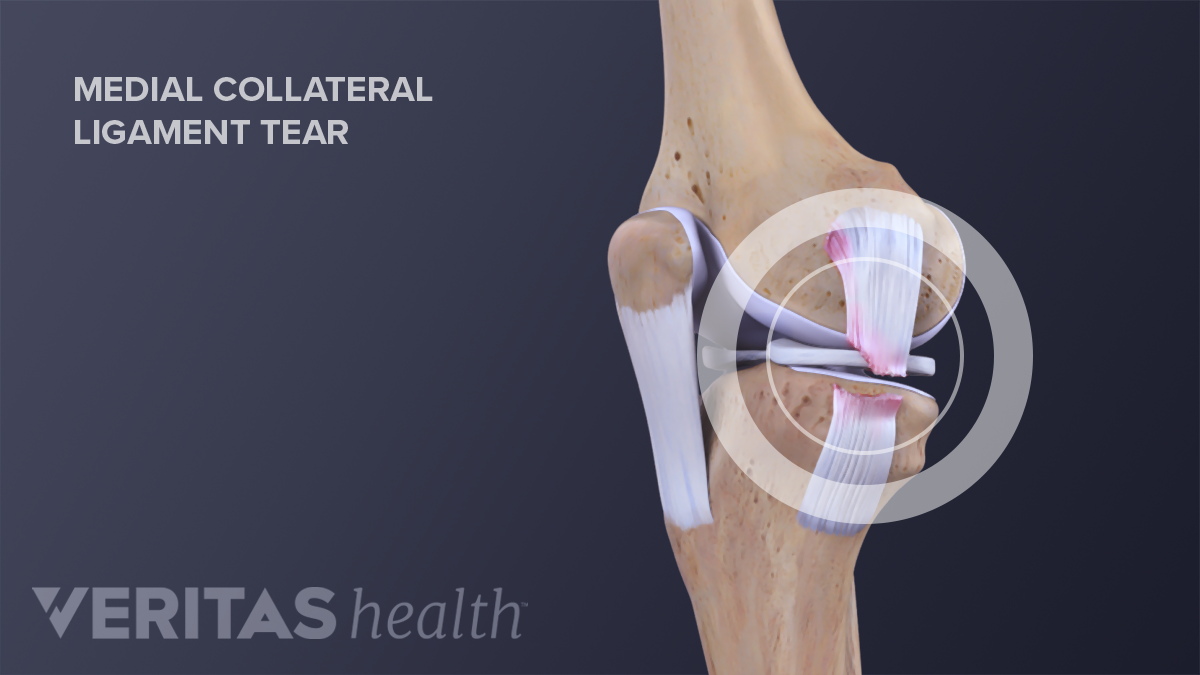

If medical treatments are not satisfactory, ligament repair surgery may be an effective treatment.

Treatment options for an mcl sprain. The surgery will either repair or reconstruct the mcl. A total rupture of the mcl usually doesn’t require surgery.